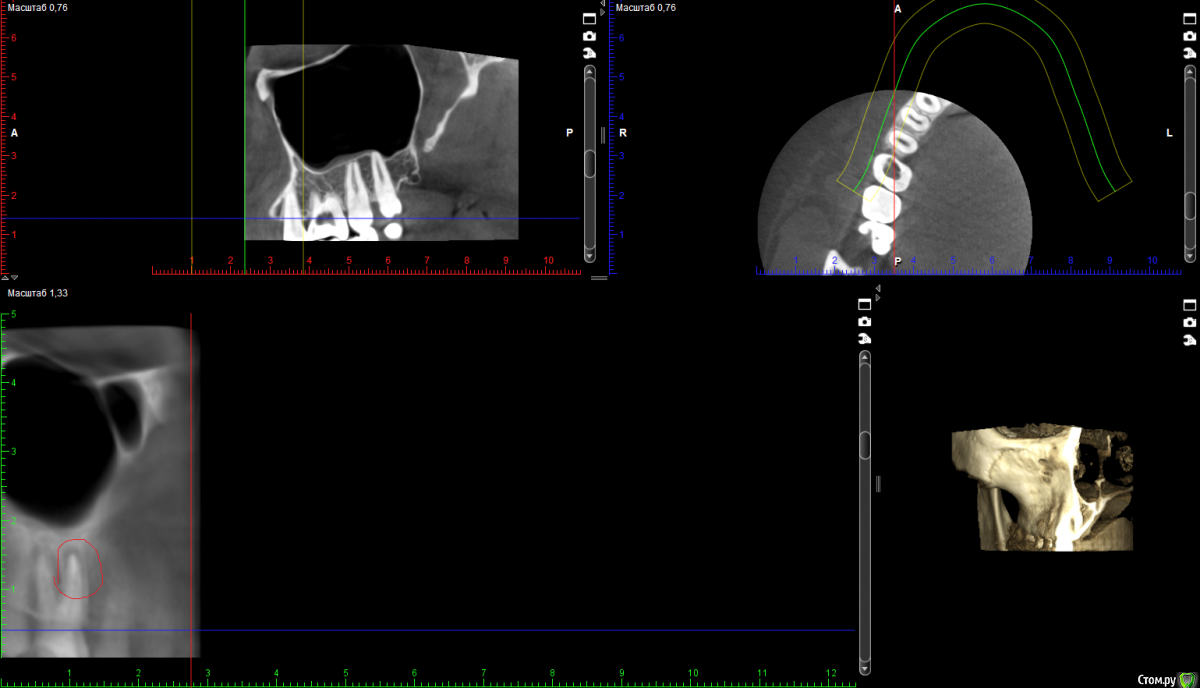

Стерхова Юлия Опубликовано 1 апреля, 2018 Автор Поделиться Опубликовано 1 апреля, 2018 Выкладываю старые срезы с опозданием(Я уже не знаю, как быть. Подскажите, пожалуйста! В общем, каналы уже месяц перелечиваются под микроскопом, диагноз - периодонтит. Примерно каждую неделю все прочищается и закладывается под временную пломбу лекарство, но результата нет - сохраняется боль в ночное время и во время очищения каналов. В гайморовой гранулёма. Несмотря на все это, хирург выступает категорически против удаления, терапевт тоже, на 7.04 запланирована пломбировка. Но на этой неделе я обратилась к ЛОРу, он поставил диагноз тонзиллит (на фоне инфицирования зуба), гайморит (из-за гранулёмы), а также нашел остаток пломбировочного материала в пазухе. Он - за удаление. Хирург наличие пломбы в пазухе отрицает. Кому верить в данной ситуации? Когда лучше сделать новое КТ: до или после пломбировки? И стоит ли пломбировать? Своим врачам я доверяю, но ЛОР заставил меня засомневаться, как и сохранение болей( Ссылка на комментарий

Стерхова Юлия Опубликовано 3 апреля, 2018 Автор Поделиться Опубликовано 3 апреля, 2018 Вот новые срезы КТ, сделанного вчера. Интересует белый кончик у канала (первый скриншот) - это резорбция? Ссылка на комментарий